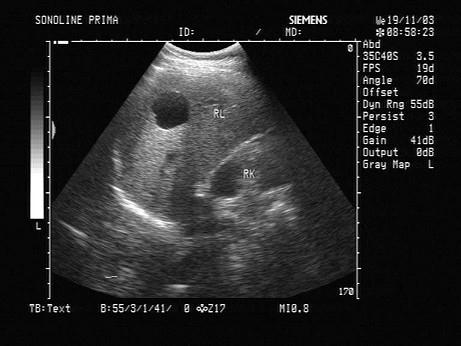

问题 男,30岁。根据超声声像图,可诊断为?(?)

选项 A.肝囊肿 B.肝包虫病 C.肝血管瘤 D.局限性脂肪肝 E.肝脓肿

答案 A